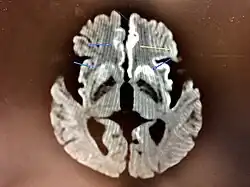

The symptoms of CJD are caused by the progressive death of the brain's nerve cells, which are associated with the build-up of abnormal prion proteins forming in the brain. When brain tissue from a person with CJD is examined under a microscope, many tiny holes can be seen where the nerve cells have died. Parts of the brain may resemble a sponge where the prions were infecting the areas of the brain.[20]

Histopathology

Testing of tissue remains the most definitive way of confirming the diagnosis of CJD, although even a biopsy is not always conclusive.[56]

In one-third of people with sporadic CJD, deposits of "prion protein (scrapie)", PrPSc, can be found in the skeletal muscle or the spleen.[57] Diagnosis of vCJD can be supported by biopsy of the tonsils, which harbor significant amounts of PrPSc; however, biopsy of brain tissue is the definitive diagnostic test for all other forms of prion disease. Due to its invasiveness, a biopsy will not be done if clinical suspicion is sufficiently high or low. A negative biopsy does not rule out CJD, since it may predominate in a specific part of the brain.[58]

The classic histologic appearance is spongiform change in the gray matter: the presence of many round vacuoles from one to 50 micrometers in the neuropil, in all six cortical layers in the cerebral cortex, or with diffuse involvement of the cerebellar molecular layer.[59] These vacuoles appear glassy or eosinophilic and may coalesce. Neuronal loss and gliosis are also seen.[60] Plaques of amyloid-like material can be seen in the neocortex in some cases of CJD.[61]

However, extra-neuronal vacuolization can also be seen in other disease states. Diffuse cortical vacuolization occurs in Alzheimer's disease, and superficial cortical vacuolization occurs in ischemia and frontotemporal dementia. These vacuoles appear clear and punched out. Larger vacuoles encircling neurons, vessels, and glia are a possible processing artifact.[58]